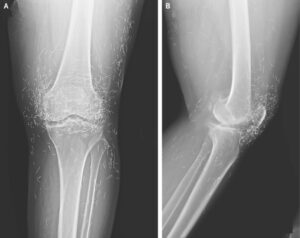

When a 65-year-old South Korean woman went in for knee pain, doctors weren’t expecting to strike gold. But that’s exactly what they found.

So she turned to acupuncture, according to a case published in the New England Journal of Medicine.

Acupuncture, a centuries-old alternative treatment, involves inserting needles into the body at specific points to relieve pain or treat illnesses. In this case, the needles— presumably made of gold — were intentionally left in her knees for continued stimulation.

He also warned that embedded needles can complicate X-ray readings. “The needles may obscure some of the anatomy,” Guermazi said in 2013.